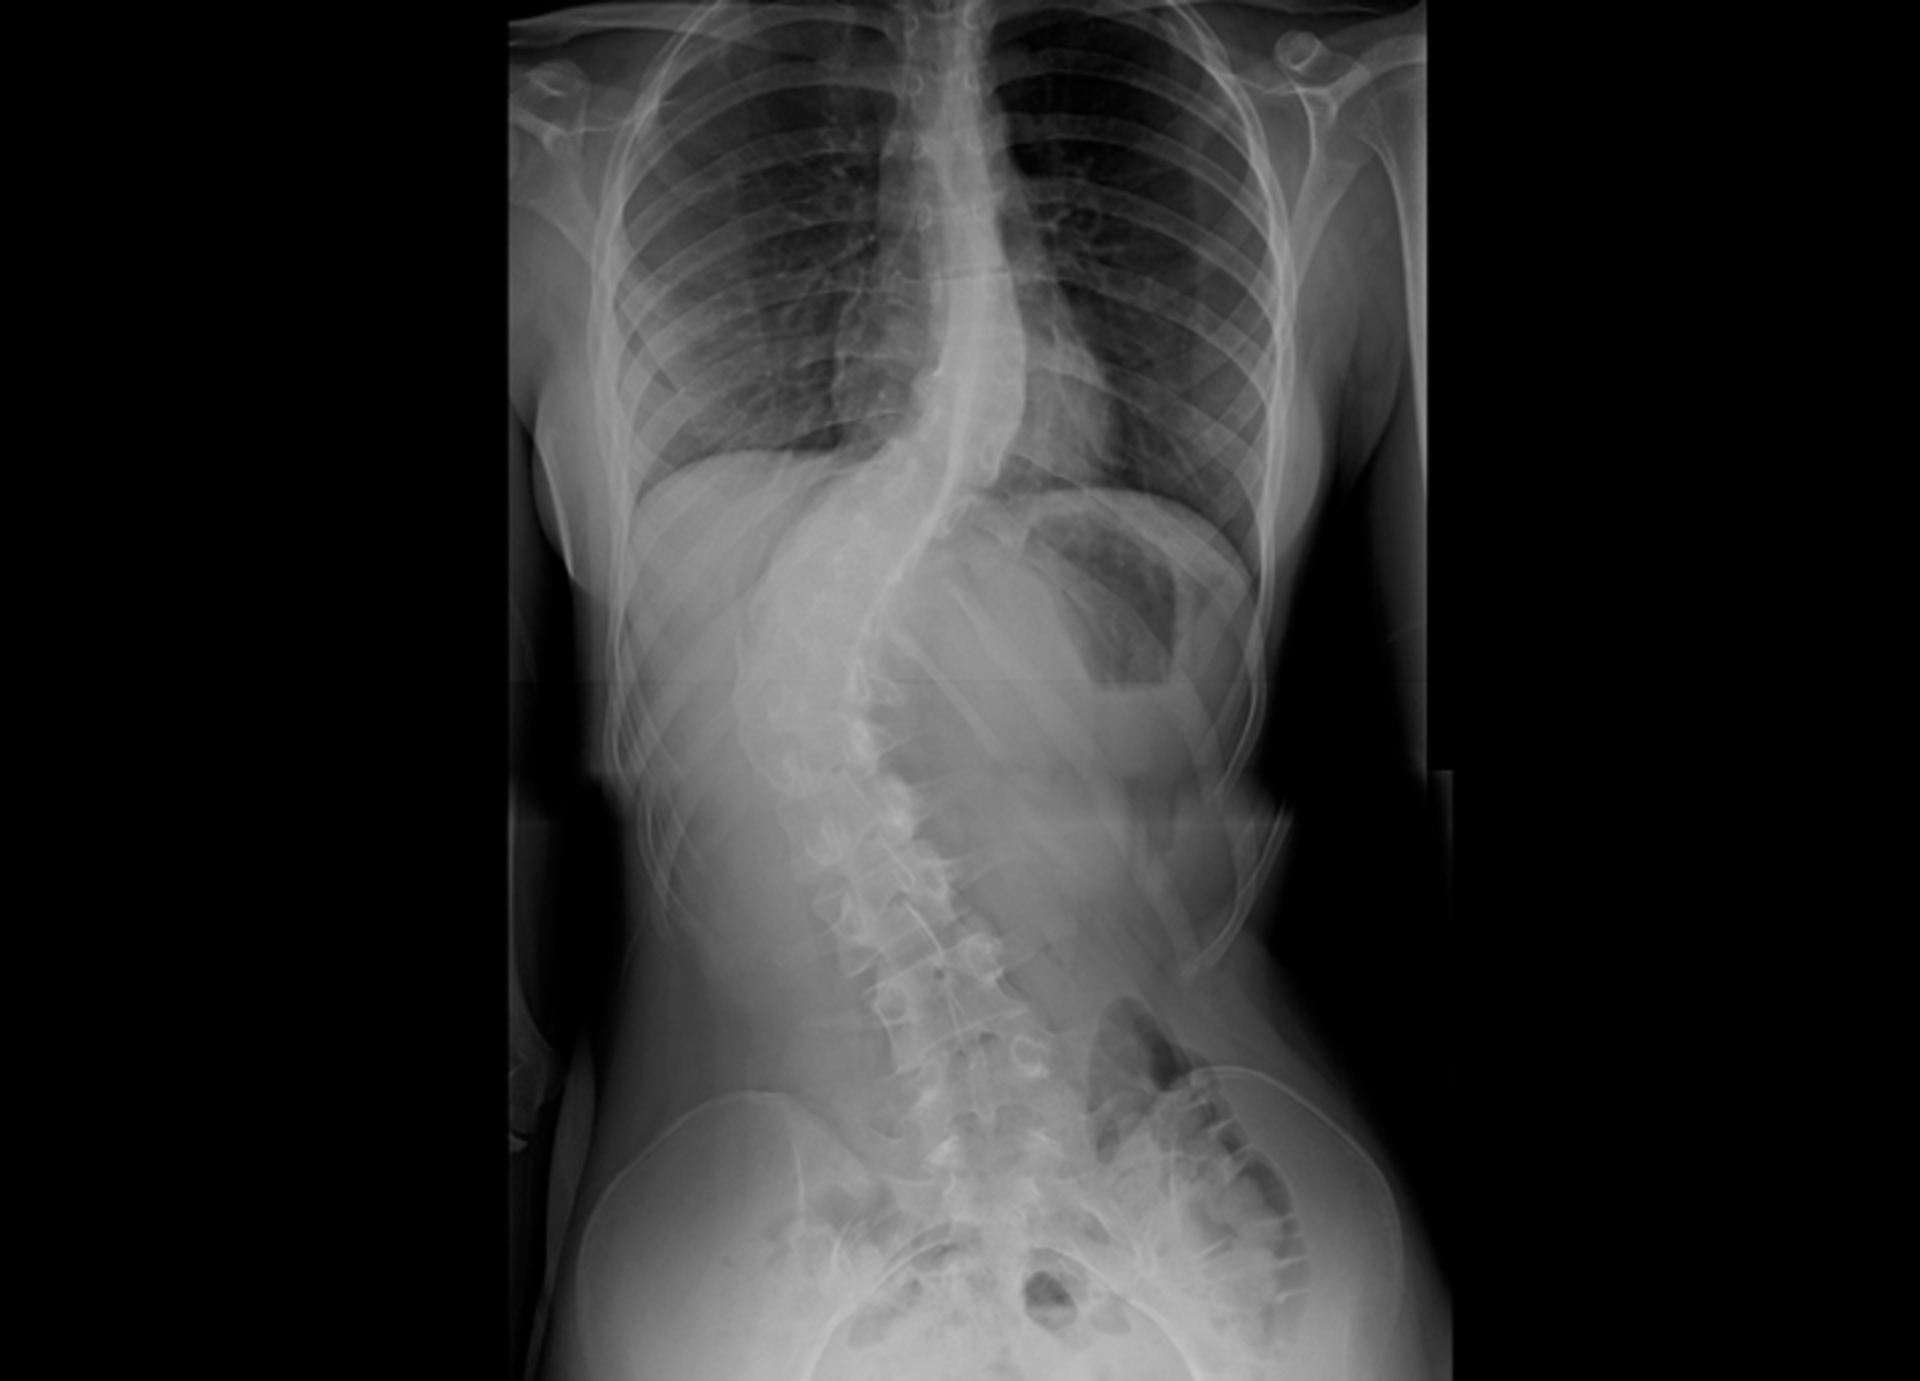

A escoliose idiopática é a curvatura lateral da coluna. O diagnóstico é clínico e inclui radiografias da coluna vertebral. O tratamento depende da gravidade da curvatura. A escoliose idiopática é a forma mais comum de escoliose e pode ser vista em 2 a 4% das crianças entre as idades de 10 e 16 anos. De acordo com a Organização Mundial da Saúde (OMS), totalizando mais de 50 milhões de crianças do mundo. No Brasil, são mais de 1,6 milhões.

Paola descobriu aos 14 anos que tinha a doença, após passar por inúmeros especialistas e realizar dezenas de exames, foi verificado que o problema se agravava com o passar dos meses. A saúde dessa jovem corre risco, pois se a cirurgia não for feita com urgência, a coluna irá se torcer cada vez mais envolta do seu próprio eixo. Hoje a curvatura está em 63° graus.